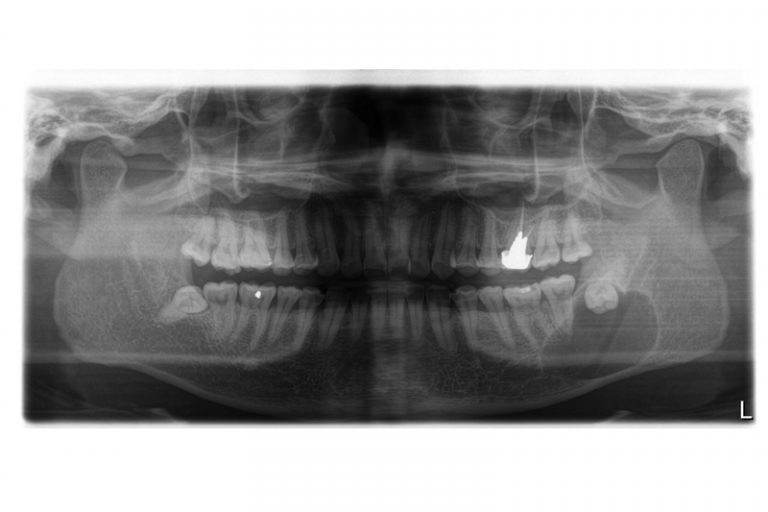

全口X光片顯示 下顎左右有阻生智慧齒

即使沒有症狀,也有隱藏問題,所以應該定期找牙醫檢查,若出現隱藏的問題,就算不痛亦應拔除智慧齒。阻生等可能會導致牙周病或蛀牙, ,令旁邊本來有用的大牙或其牙骨缺損,但當患者開始疼痛的時候才處理已經太遲。因此建議在18至20歲左右前往牙醫診所檢查並拍攝一張X光片,判斷是否有阻生並需要剝牙。大部份人的智慧齒也沒有足夠位置長出,在有限的空間下成長會導致阻生,無論它生長的角度如何都可能導致上述口腔的問題。

值得注意的是,智慧齒阻生或令組織病變而形成囊腫,因此別以為不痛不癢便無須理會智慧齒。

智慧齒阻生令顎骨內其他組織病變而形成顎骨囊腫